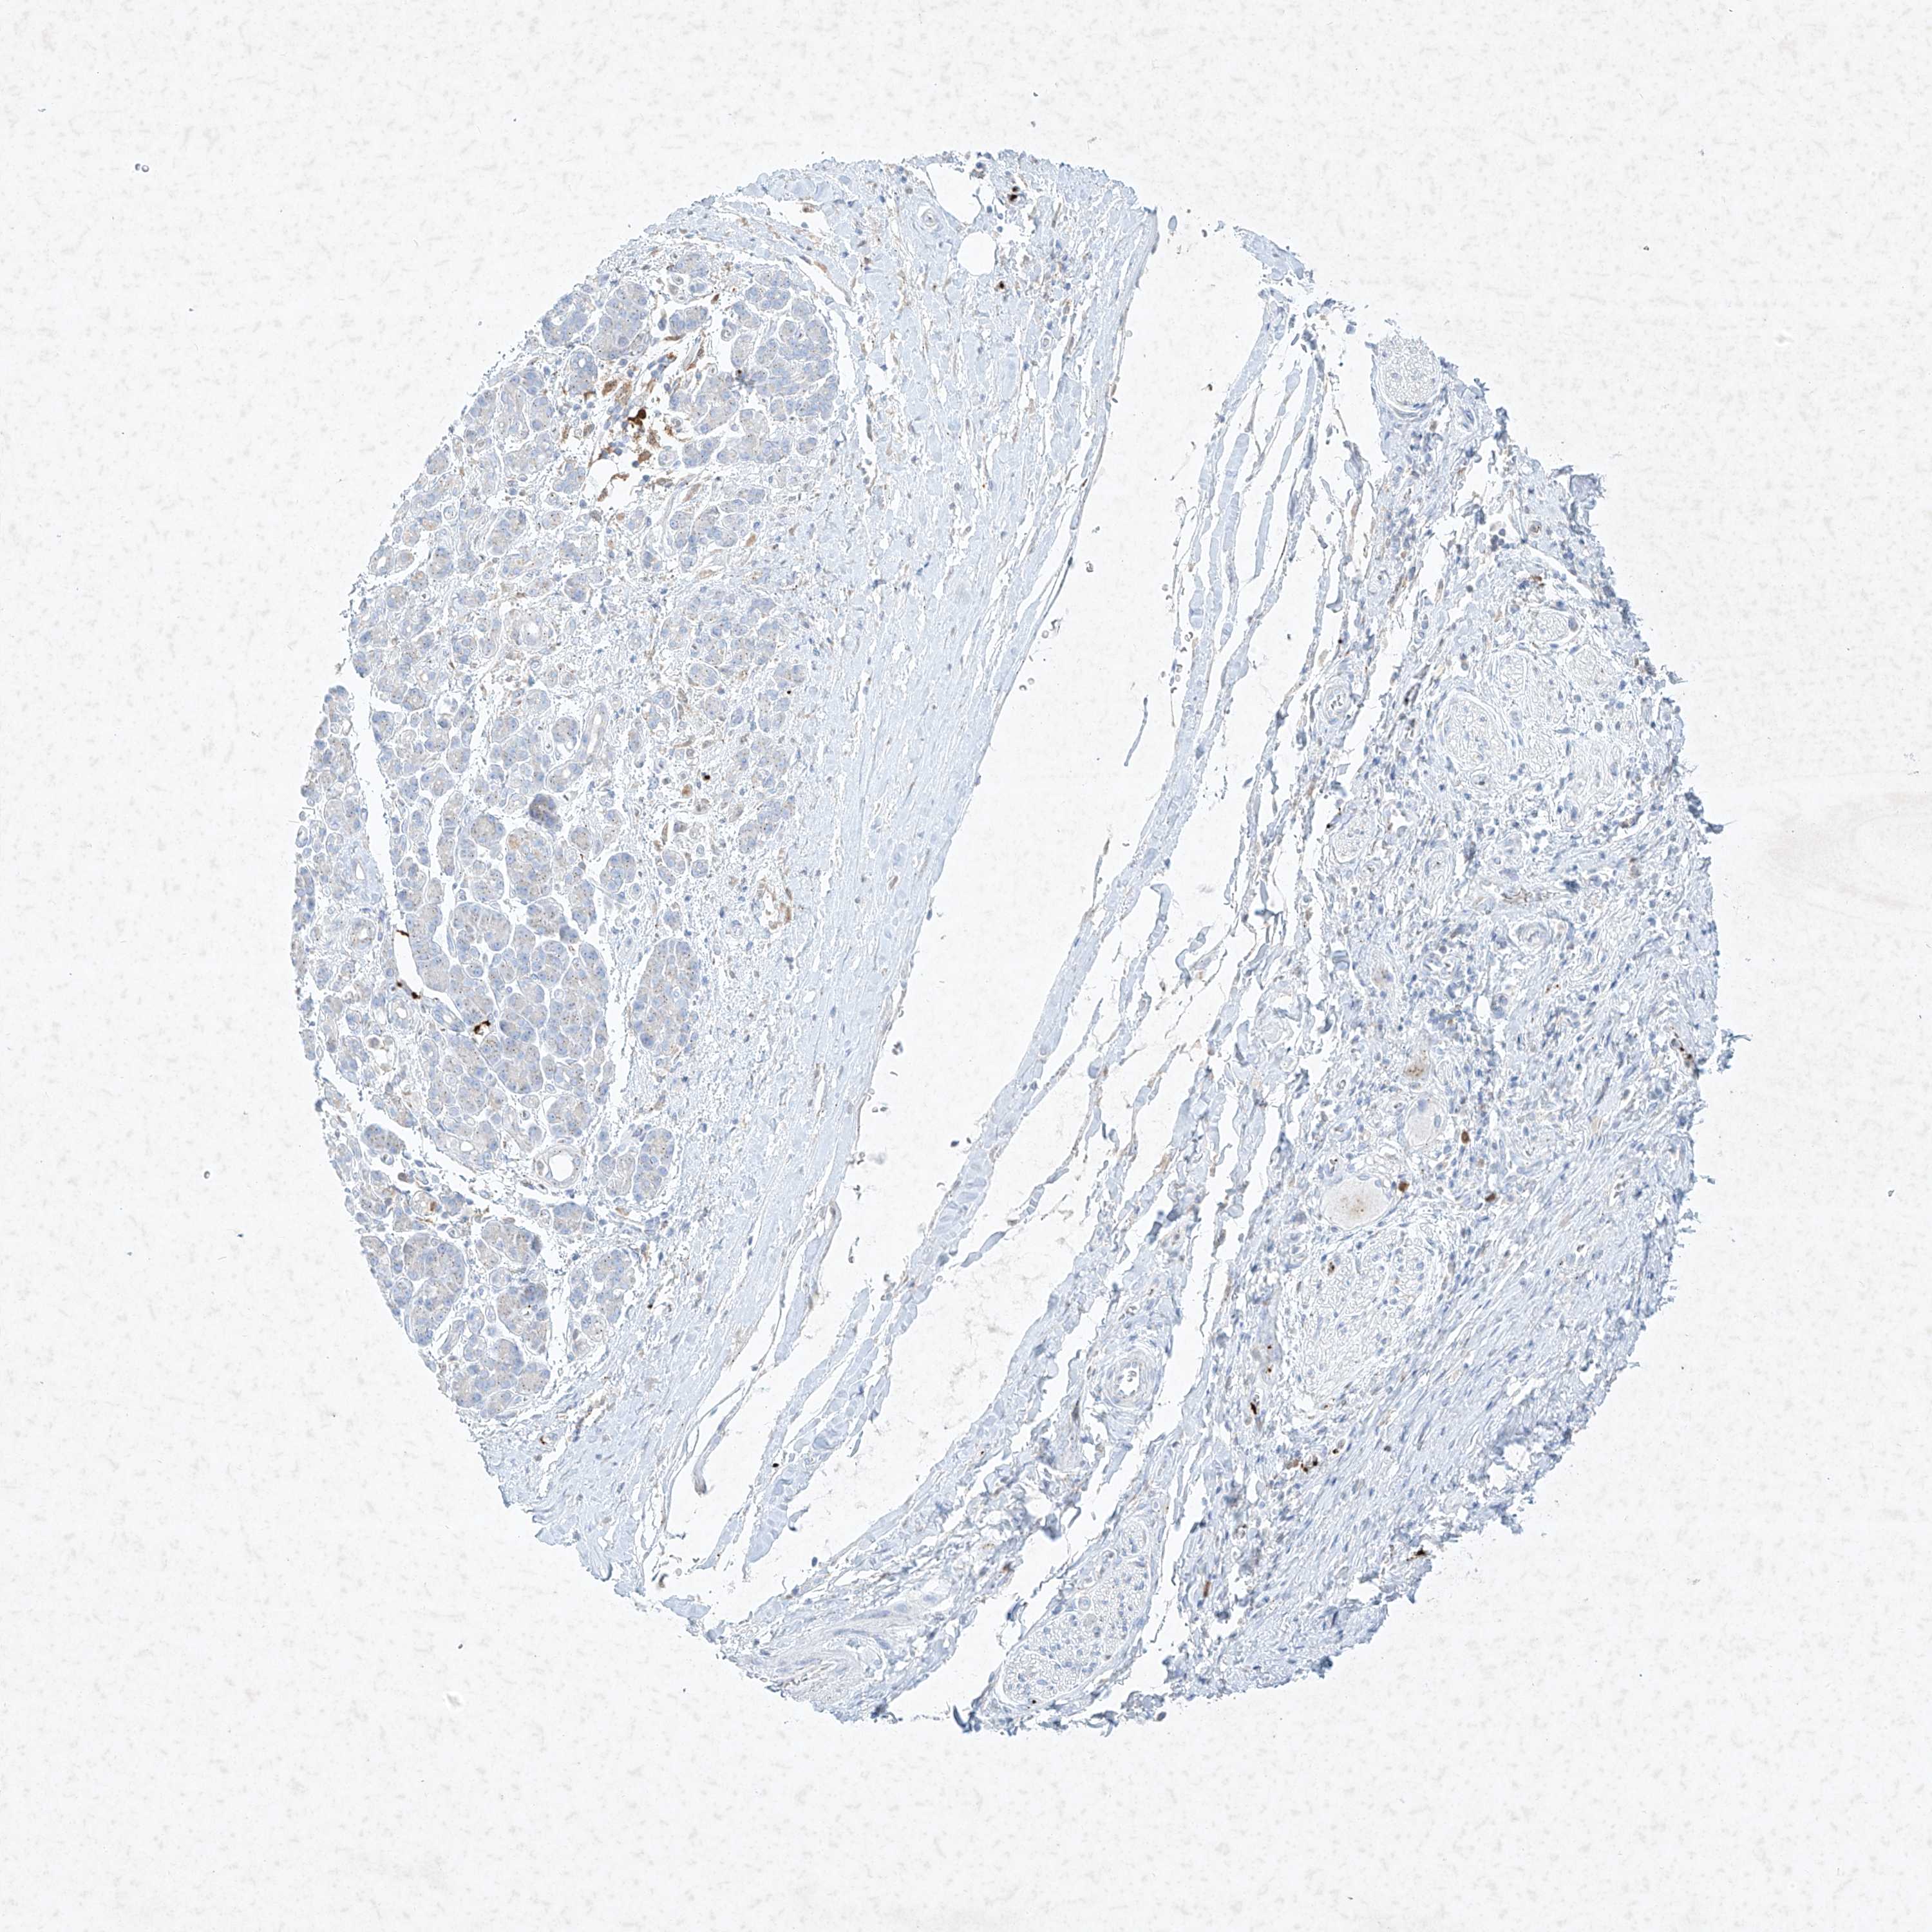

PANCREATIC CANCER - Protein expressioni

A mouse-over function shows sample information and annotation data. Click on an image to view it in a full screen mode. Samples can be filtered based on level of antibody staining by selecting one or several of the following categories: high, medium, low and not detected. The assay and annotation is described here.

Note that samples used for immunohistochemistry by the Human Protein Atlas do not correspond to samples in the TCGA dataset.

Antibody stainingi

Antibody staining in the annotated cell types in the current human tissue is reported as not detected, low, medium, or high, based on conventional immunohistochemistry profiling in selected tissues. This score is based on the combination of the staining intensity and fraction of stained cells.

Each image is clickable and will lead to virtual microscopy that enables deeper exploration of all samples and also displays staining intensity scores, fraction scores and subcellular localization as well as patient and tissue information for each sample.

Antibody HPA031838

Antibody HPA057341

Adenocarcinoma, NOS